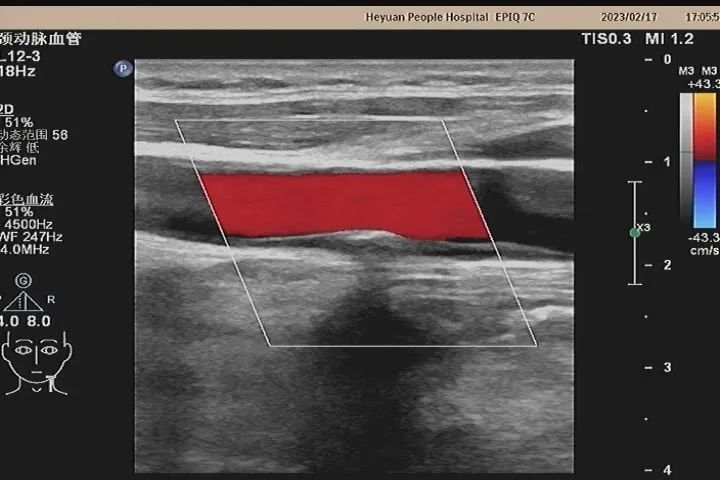

超声医生利用彩超仪器获得血管的实时动态图像,观察血管的解剖结构、血流动力学状态来诊断疾病。由于它方便快捷、无创、没有辐射等优点,血管超声检查又被称为无创伤性的血管造影术。临床医生常把它作为对头颈部及四肢血管疾病的首选检查。

(1)颈部血管疾病:如有头晕、头痛等症状,疑为颈、椎动脉狭窄和闭塞性疾病引起。